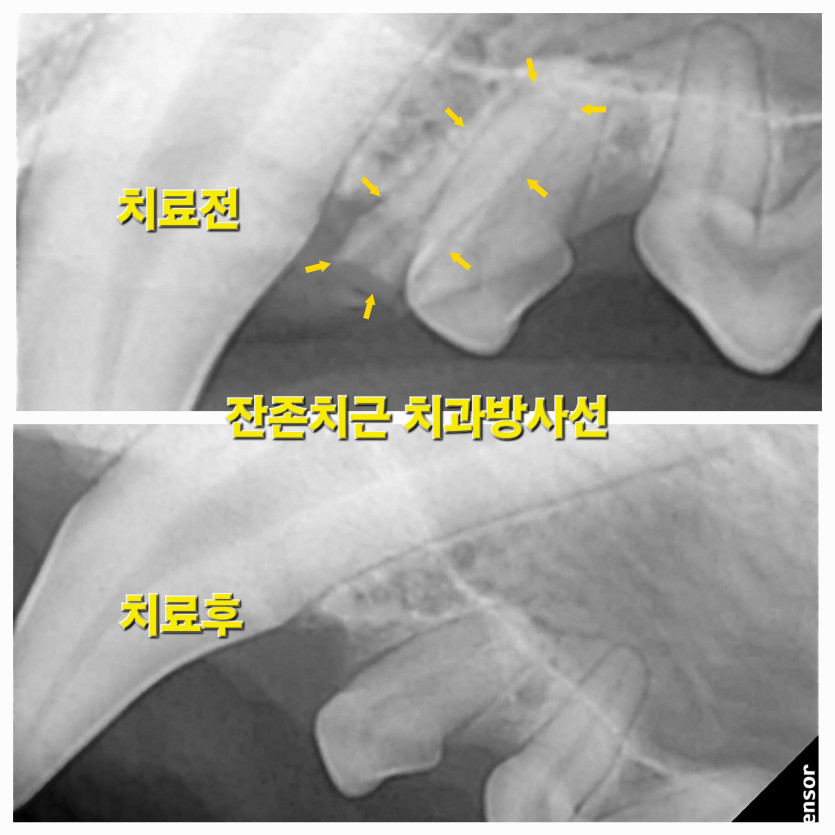

리오의 잔존유치 무통발치 치료후기

유치발치를 진행하였는데, 걱정하지 않게 아이 사진도 중간에 보내주시고 진행상황도 카톡으로 안내해주셔서 한결 걱정을 덜 한것 같다. 발치 수술도 잘 되었고 아이도 문제없이 회복했다.

항상 아이를 배려해주시고 먼저 생각해주시는 것 같다.